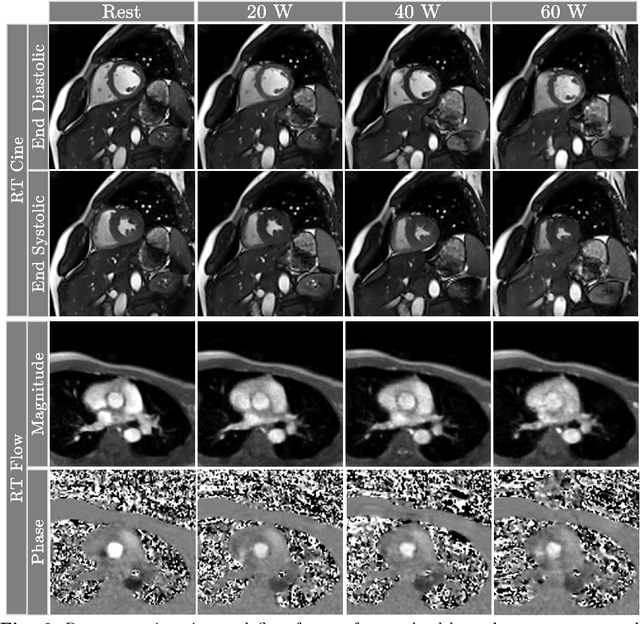

Abstract:Background: Cardiovascular magnetic resonance imaging (CMR) is a well-established imaging tool for diagnosing and managing cardiac conditions. The integration of exercise stress with CMR (ExCMR) can enhance its diagnostic capacity. Despite recent advances in CMR technology, ExCMR remains technically challenging due to motion artifacts and limited spatial and temporal resolution. Methods: This study investigates the feasibility of biventricular functional and hemodynamic assessment using real-time (RT) ExCMR during a staged exercise protocol in 26 healthy volunteers. We introduce a coil reweighting technique to minimize motion artifacts. In addition, we identify and analyze heartbeats from the end-expiratory phase to enhance the repeatability of cardiac function quantification. To demonstrate clinical feasibility, qualitative results from five patients are also presented. Results: Our findings indicate a consistent decrease in end-systolic volume (ESV) and stable end-diastolic volume (EDV) across exercise intensities, leading to increased stroke volume (SV) and ejection fraction (EF). Coil reweighting effectively reduces motion artifacts, improving image quality in both healthy volunteers and patients. The repeatability of cardiac function parameters, demonstrated by scan-rescan tests in nine volunteers, improves with the selection of end-expiratory beats. Conclusions: The study demonstrates that RT ExCMR with in-magnet exercise is a feasible and effective method for dynamic cardiac function monitoring during exercise. The proposed coil reweighting technique and selection of end-expiratory beats significantly enhance image quality and repeatability.